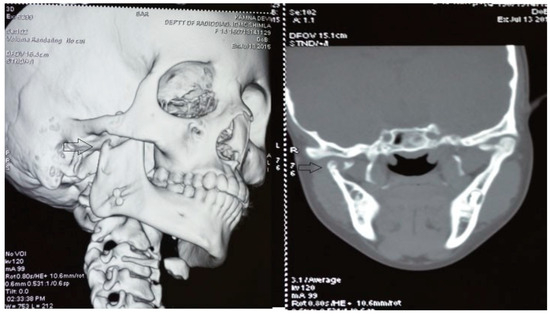

A retrospective study of post–ankylotic TMJ reconstruction of all the patients who underwent surgery for the TMJ ankylosis over a period of 11 years from 2002 to 2013, which were operated by the senior author (Y.B.), was undertaken to evaluate demographics, type of TMJ ankylosis, and modality of post–ankylotic TMJ reconstruction. The following inclusion criteria were considered for enrolling patients in this study: (1) history of traumatic injury to the face or jaws; (2) clinical and radiographic evidence of bony ankylosis at the time of presentation; (3) reconstruction of the TMJ using autogenous or alloplastic material after surgical release of ankylosis. Patients were assessed for (1) maximum interincisal opening pre and post operatively; (2) restored vertical ramal height; (3) occlusion; (4) facial symmetry; and (5) postoperative complications. Radiographic evaluation consisted of both preoperative and postoperative panoramic radiography Orthopentomogram (OPG) (Figure 1 and Figure 2) and CT scans in axial, coronal, and sagittal sections with three-dimensional reconstruction (Figure 3 and Figure 4). Surgical protocol was that the TMJ was approached through the Al-Kayat and Bramley’s incision and at least 2 to 2.5 cm resection of the ankylotic chunk was performed in all our cases. Ipsilateral and contralateral coronoidectomy was performed when required to achieve passive mouth opening. Interpositional arthroplasty was done using various materials such as temporalis fascia, temporalis muscle, and articular disc, whereas joint reconstruction was done using CCG and titanium reconstruction plate with condylar head. Intensive physiotherapy postoperatively was an integral part of protocol.

Figure 4. Postoperative coronal CT and three-dimensional CT scan with temporomandibular joint (TMJ) ankylosis at 6 years of follow-up depicting neocondyle (black arrow) formation (CCG graft with temporalis muscle interpositioning was done with respect to right TMJ).